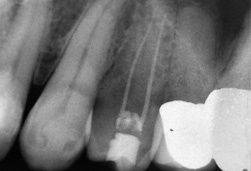

Die erste Aufnahme zeigt eine gute, aber leider nicht erfolgreiche Wurzelbehandlung. 2 Jahre nach Abschluss der Behandlung bereitete der Zahn wieder starke Schmerzen. Die Behandlungsmöglichkeiten waren dann: Zahn entfernen, eine chirurgischen Wurzelspitzenresektion vornehmen zu lassen oder die Wurzelbehandlung durch einen Spezialisten erneuern zu lassen. Die zweite Aufnahme zeigt den gleichen Zahn nach Abschluss der zweiten Wurzelbehandlung, einer sog. Revision. Der Zahn ist seit der Neubehandlung beschwerdefrei.

Zu sehen ist die unterschiedliche Dicke der Wurzelfüllung (der weiße Strich im Zahn) und die unterschiedliche Länge der Wurzelfüllung; nach der erneuten Behandlung ist der Wurzelfüllung länger und folgt dem Verlauf des Wurzelkanals an der Wurzelspitze in einer Kurve.